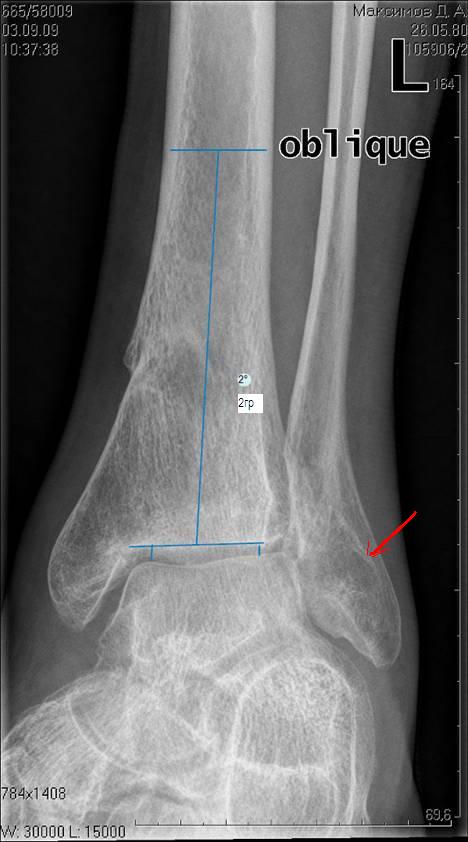

[Ortho] три картинки к моему сообщению "очередной посттравматический артроз голеностопного сустава)

Вложение не в текстовом формате было извлечено…

Имя     : Мортиз - проекция 0.JPG

Тип     : image/jpeg

Размер  : 49037 байтов

Описание: отсутствует

Url     : http://weborto.net:8080/pipermail/ortho/attachments/20090903/35ba3f6d/attachment-0003.jpeg